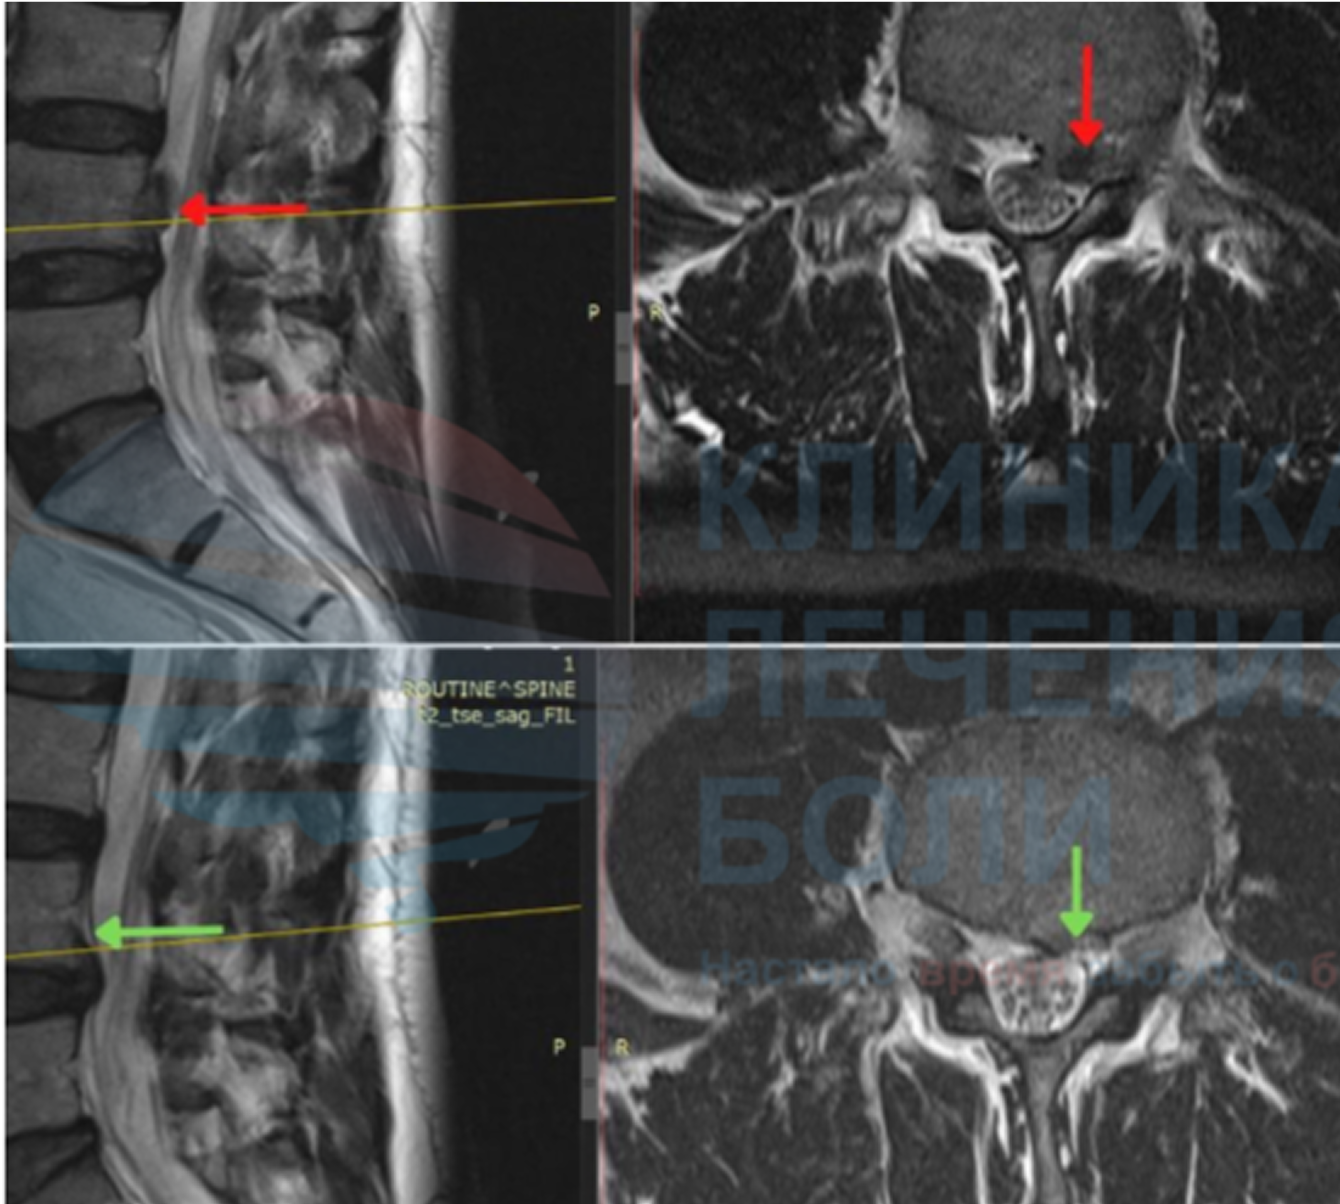

Безоперационное лечение позвоночника и боли в спине.

Мы специализируемся на современном безоперационном лечении боли в спине и суставах. Благодаря нашим методикам тысячи пациентов избежали операции и улучшили качество жизни.

Метод безоперационного уменьшения или полного исчезновения грыжи межпозвонкового диска